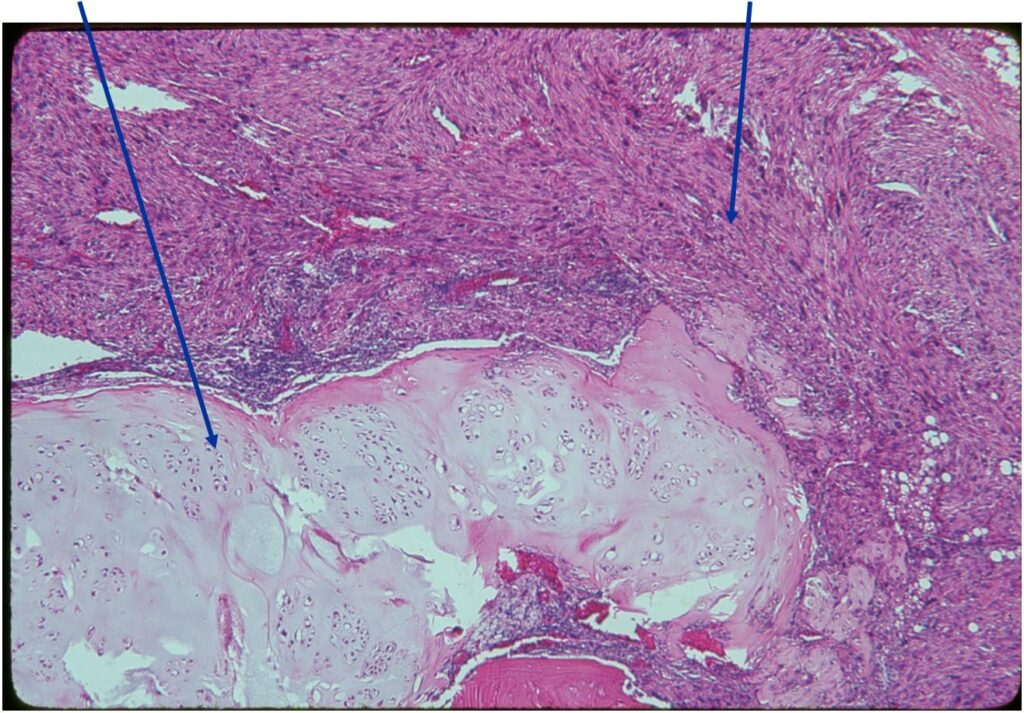

Dedifferentiated chondrosarcoma consists of a low grade malignant hyaline cartilage tumor associated with a high-grade nonchondroid spindle sarcoma. The two components are juxtaposed with abrupt clear demarcation line

Junction of cartilaginous and noncartilaginous components is sharp and distinct. There are no dedifferentiated areas admixed in the middle of the cartilaginous areas

(Top Arrow) High Grade Dedifferentiated Spindle Cell Sarcoma Component

(Left Arrow) Low Grade Cartilage Component

(Right Arrow) Low Grade Cartilage Component